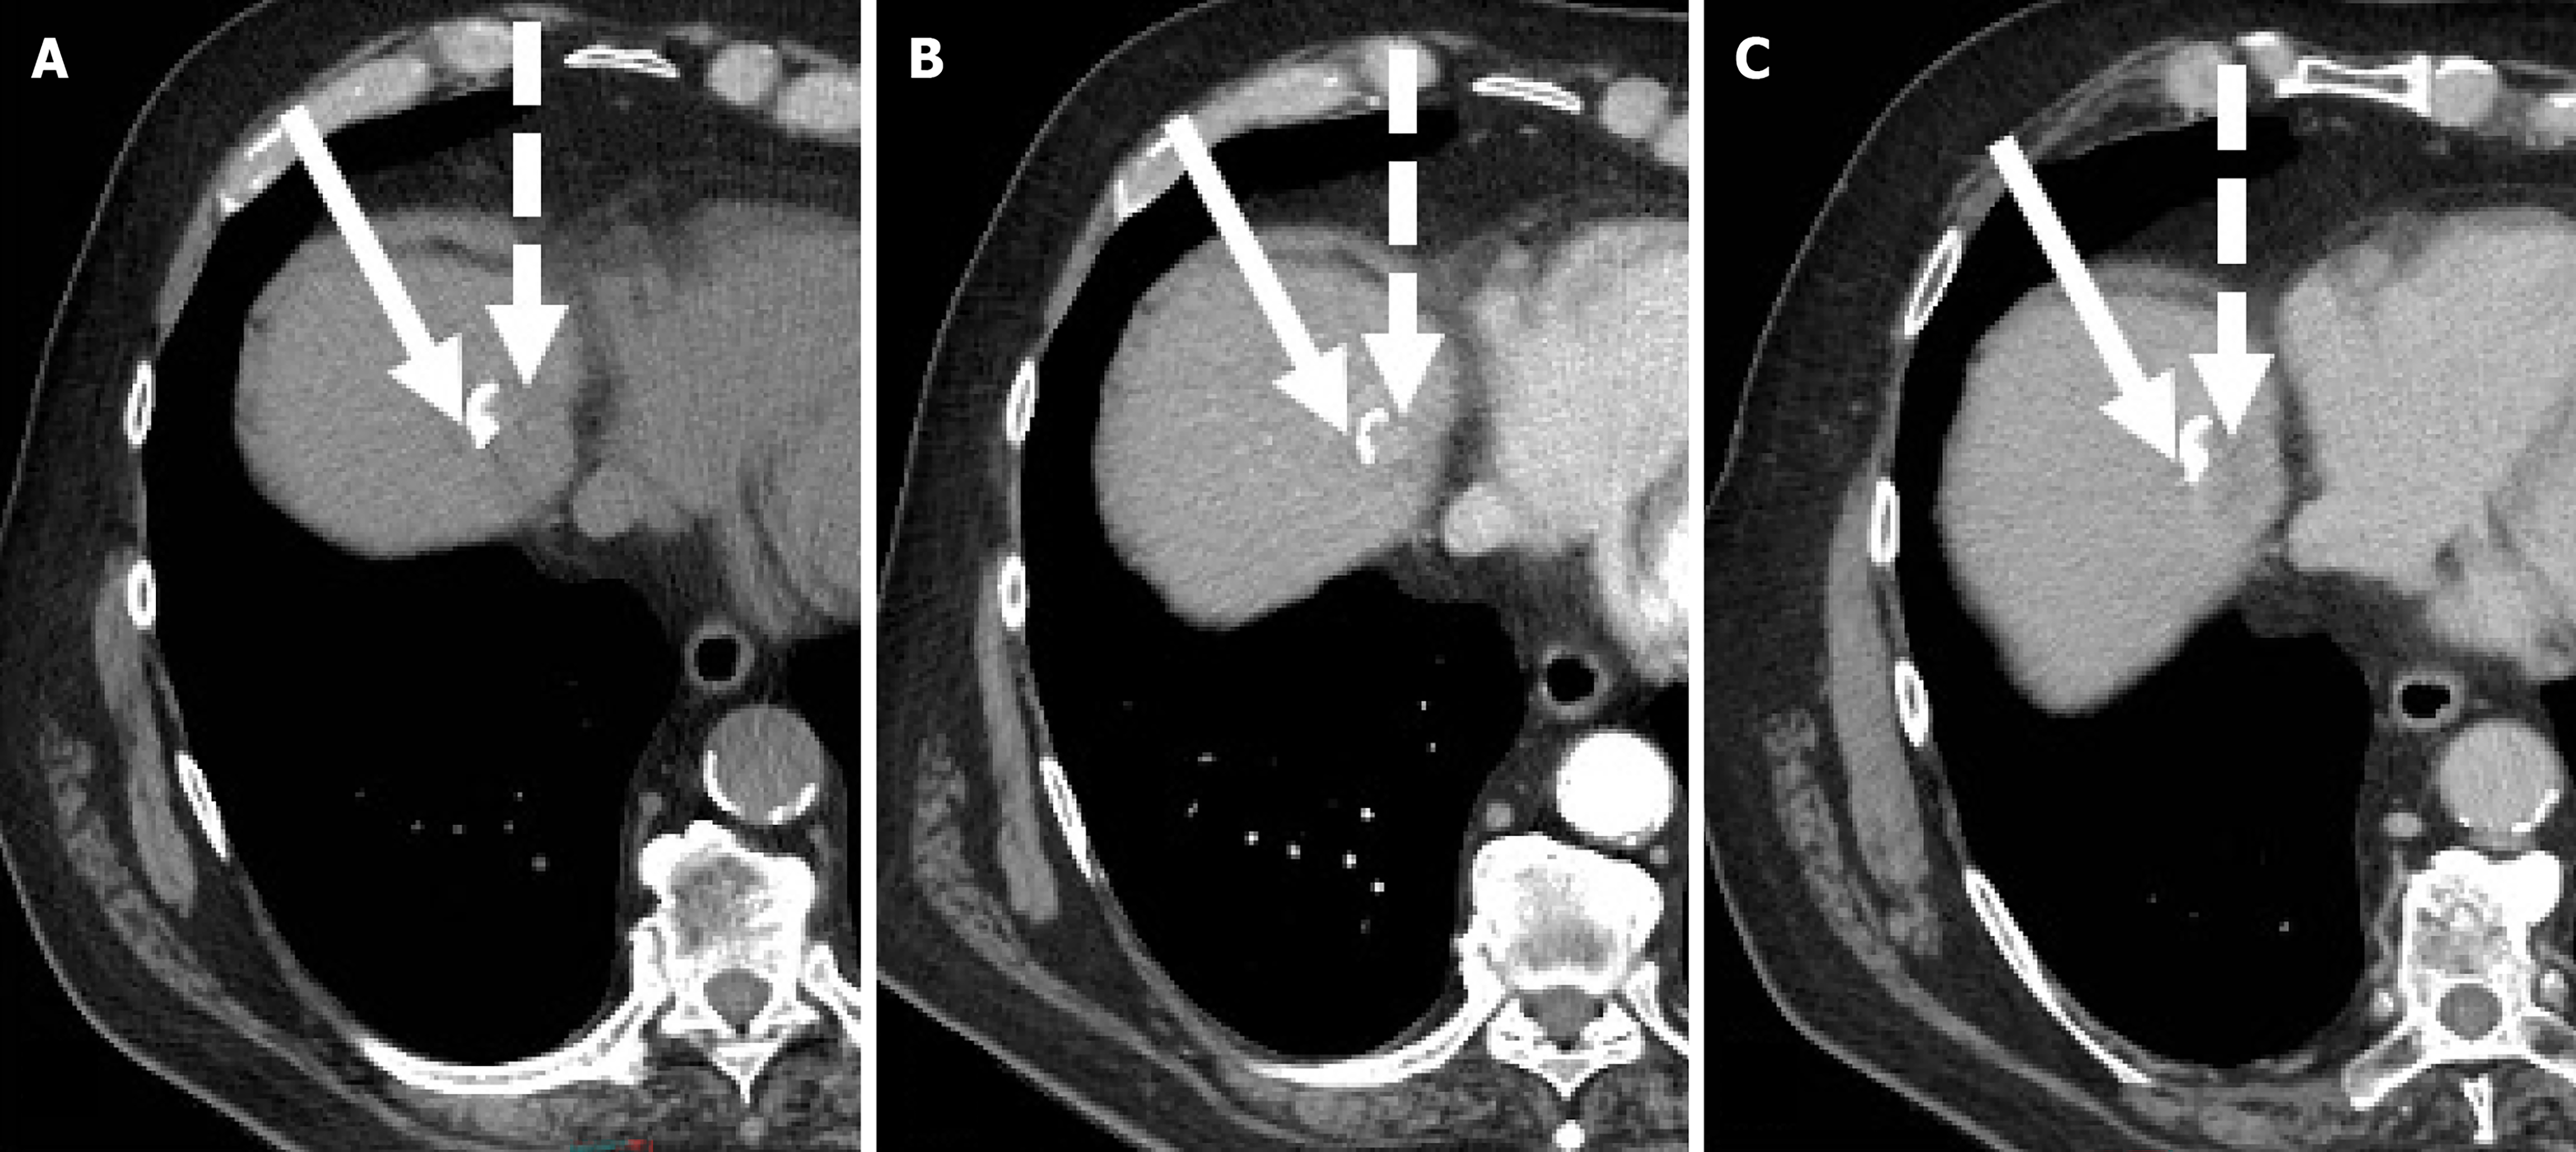

Figure 3 Residual hepatocellular carcinoma after radiofrequency ablation in a 68-year-old man with hepatitis C virus-related hepatic cirrhosis.

A: On magnetic resonance imaging obtained one month after radiofrequency ablation the treated area (arrow) shows slight hyperintensity on unenhanced T1-weighted due to coagulative necrosis; B: On corresponding hepatic arterial phase (HAP) image the treated area shows heterogenous hyperintensity; C: Subtracted HAP image shows enhancement in the posterior portion of the treated area (dotted arrow) suggesting residual tumor enhancement.